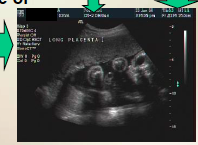

what plane was this scanned in?

how far along is this GA? Why?

Note this longitudinal view of the thorax & abdomen that is later in the gestational age - the lungs are now hyperechoic compared to the liver